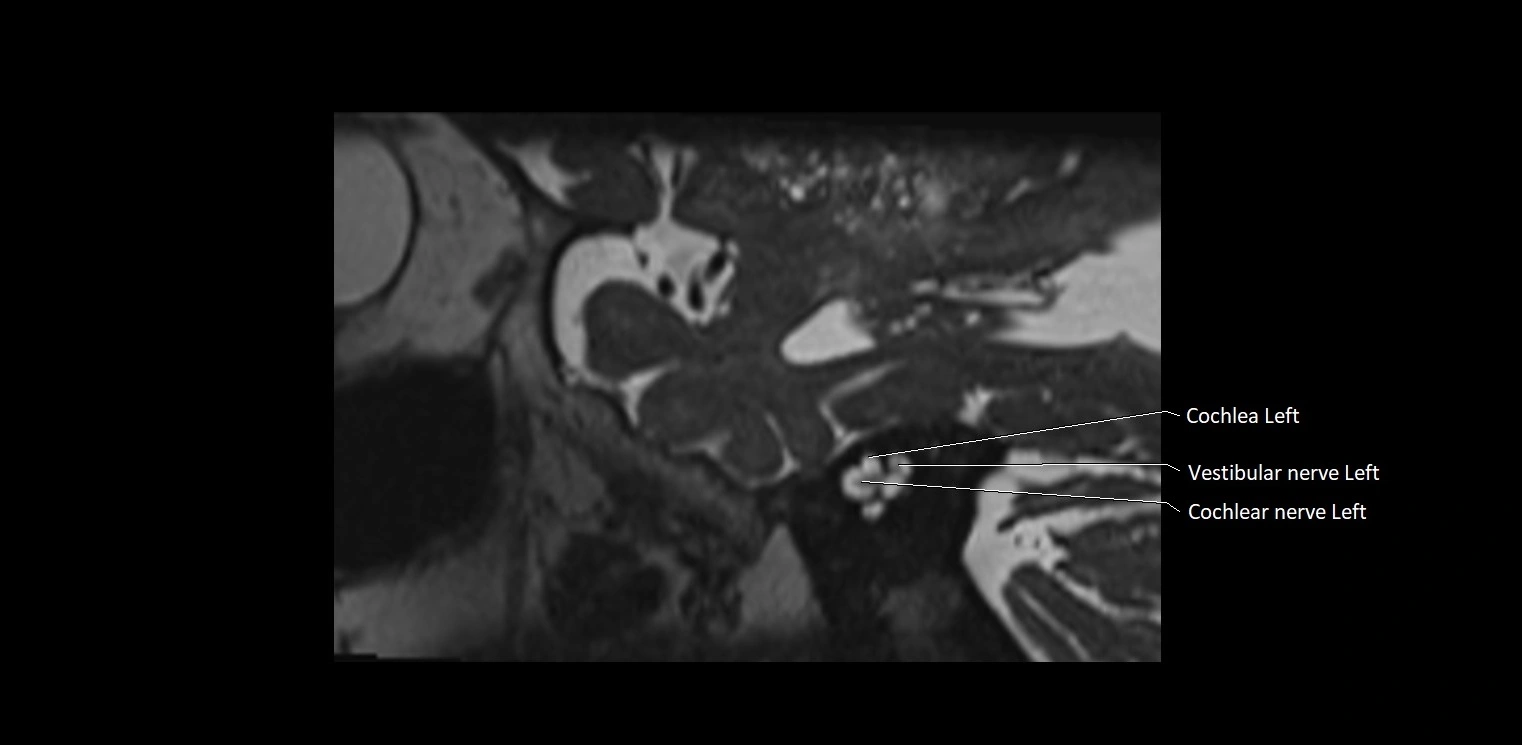

MRI Appearance

• The abducens nerve is a small, thin, linear structure

• Best visualized on high-resolution T2-weighted 3D MRI sequences (e.g., FIESTA or CISS)

• Seen as a hypointense (dark) line running from the brainstem at the pontomedullary junction, traversing the prepontine cistern, and entering Dorello’s canal under the petrosphenoidal ligament, then into the cavernous sinus, and finally the orbit

• May be challenging to visualize in standard MRI due to its small size

• Pathology may be inferred by absence, displacement, or enhancement of the nerve

MRI images

image